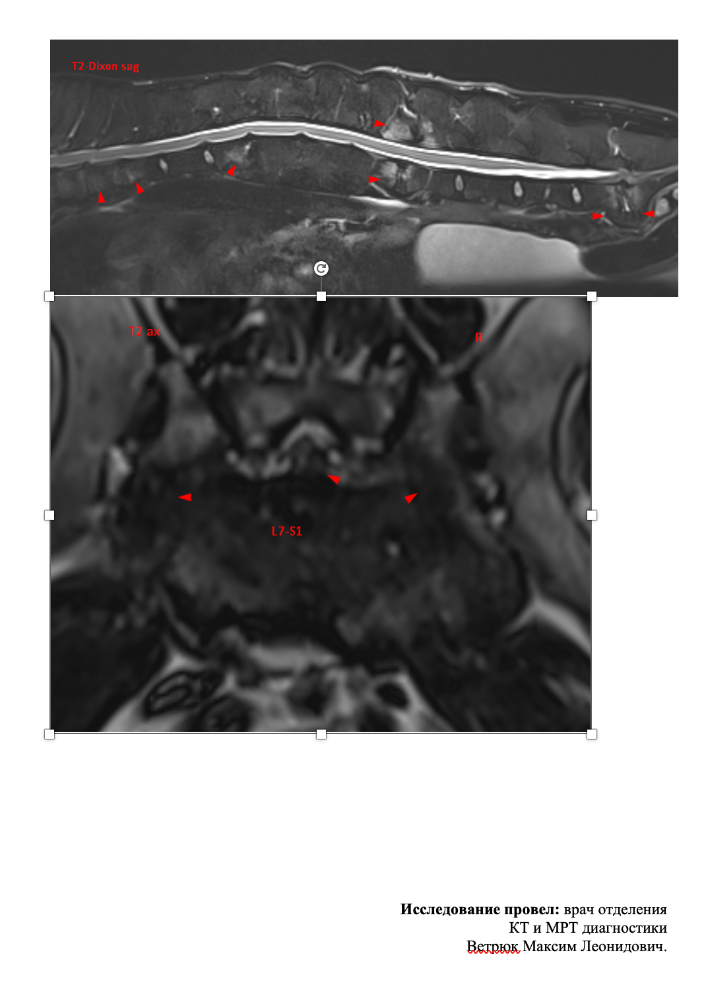

Mosfilmka & Remy Опубликовано 12 мая, 2022 Опубликовано 12 мая, 2022 (изменено) К сожалению, хороших новостей у нас нет... Мы сделали МРТ, результат ниже. Простынь перечисленных проблем... С этим мы пошли к Курганской, уже без Гуру, потому что мотать его туда-сюда снова и трясти в машине ну совсем уже не хотелось. Итог - уколы нам делать нельзя, позвоночный столб воспален, несмотря на долгую антибиотикотерапию. Делать операцию на проблему зада - вся нагрузка упадет на перед, боимся, он просто этого не выдержит. И после этой операции последует операция на перед как заживет зад... Сменили антибиотик по назначению доктора. В общем, все очень печально, ребенок не может сам ходить, лапы отказывают... Дела делает с поддержкой. ?Арине и Сергею низкий поклон за заботу о старичке!! Вспоминаю Старочку и понимаю - как это - ухаживать за собакой, которая постепенно обездвиживается... Баланс 35 141₽ Пополнения: 200руб Лада-Ладушка 3100руб ВИКТОРИЯ 2000руб Печатный экспресс 1300руб пенсия апрель 10000руб пенсия май Итого пополнения: 16600руб Расходы: 528руб аптека 10000руб зоотакси туда-обратно 18500руб МРТ 3500руб прием Курганской Итого расходы: 32528руб ИТОГО БАЛАНС: 19 213₽ Изменено 12 мая, 2022 пользователем Mosfilmka & Remy 3